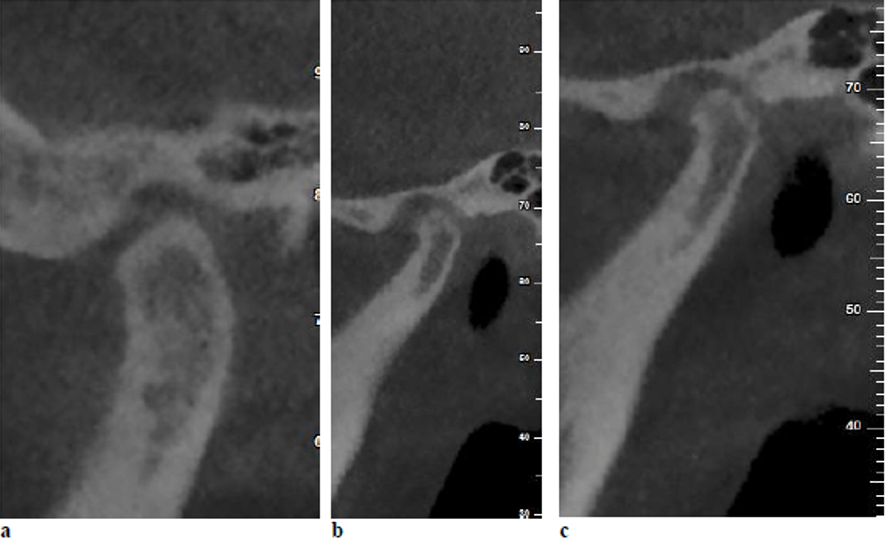

Estudios previos han informado que varios pacientes con trastornos de la ATM podrían sufrir cambios anatómicos en los tejidos óseos y/o blandos de la articulación temporomandibular. La anatomía de la ATM podría evaluarse mediante diversas técnicas, entre ellas la radiografía panorámica, la radiografía transcraneal, la tomografía computarizada de cone beam (TCCB) y la resonancia magnética (RM). La TCCB es una modalidad fiable para la evaluación de los defectos óseos de la ATM y esta es comparable a la tomografía computarizada (TC) en cuanto a precisión. Las imágenes de la ATM obtenidas mediante TCCB pueden proporcionar mucha información sobre los cambios óseos, incluyendo osteofitos, erosión, aplanamiento, esclerosis del hueso subcondral, anquilosis y seudoquistes.

En cuanto a los cambios óseos, no se encontraron diferencias significativas entre los pacientes con disfunción temporomandibular y los grupos asintomáticos en el presente estudio, que utilizó CBCT como herramienta de diagnóstico. Este hallazgo podría poner de relieve que las manifestaciones clínicas de los trastornos de la ATM muestran una escasa correspondencia con las alteraciones internas identificadas en las imágenes radiográficas. En consonancia con este hallazgo, Petersson, en un estudio de revisión, afirmó que los hallazgos radiológicos de la ATM podrían no correlacionarse constantemente con los hallazgos clínicos en pacientes con trastornos de la ATM. Además, Palconet informo de una escasa correlación entre los cambios estructurales en las imágenes TCCB y los signos y síntomas clínicos en los trastornos de la ATM. Magnus, en una serie de radiografías panorámicas correspondientes a pacientes con trastornos de la ATM, informaron de hallazgos radiográficos clínicamente relevantes relacionados con la ATM en el 25 % de los casos, mientras que el 11 % mostró hallazgos radiográficos relevantes no relacionados con trastornos de la ATM. Por el contrario, Cevi-danes encontró los pacientes con sintomatología dolorosa en la ATM tenían una frecuencia significativamente mayor de cambios condilares degenerativos en comparación con los individuos asintomáticos.

Shahidi, S., Salehi, P., Abedi, P., Dehbozorgi, M., Hamedani, S., & Berahman, N. (2018). Comparison of the bony changes of TMJ in patients with and without TMD complaints using CBCT. Journal of Dentistry, 19(2), 142.